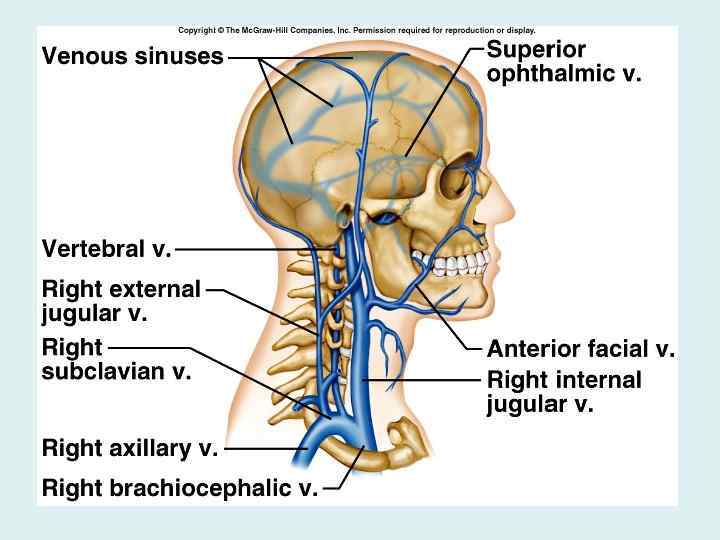

Внутренняя яремная вена • Собирает кровь от головы и шеи, из бассейна наружной и внутренней сонных и позвоночных артерий • Исток: сигмовидный синус • Притоки: внутричерепные и внечерепные

Внутричерепные притоки • • • Синусы твердой мозговой оболочки диплоические вены, глазные вены, вены лабиринта, мозговые вены, вены оболочек

Внечерепные притоки • • • Лицевая вена Позадичелюстная вена Глоточные вены Язычная вена Верхние щитовидные вены Средняя щитовидная вена

Подключичная вена • Собирает кровь из затылочной, заушной, передней области шеи • Исток – является продолжением подмышечной вены • Притоки: наружная яремная вена, передняя яремная вена, грудные вены